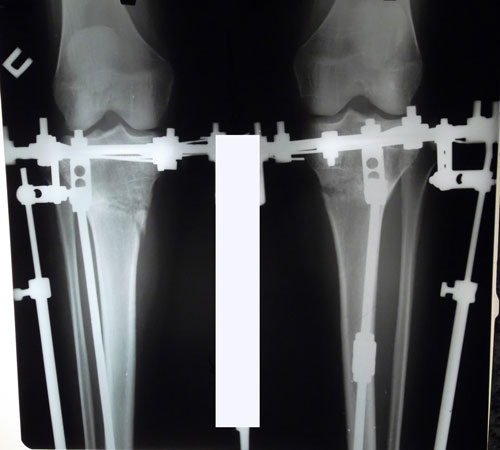

РЕНТГЕН ДО ОПЕРАЦИИ